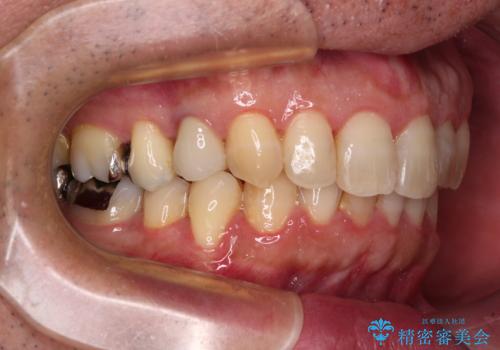

- 外に飛び出した側方の歯と、前歯のデコボコを気にして来院された患者様です。

IPR(歯と歯の間を削る)によってデコボコが解消するように設計し、インビザラインにより治療を行うこととしました。

治療途中で1年半以上通院されない時期があったため、後戻りが生じたことで治療期間が長くなってしまいました。

親知らずを抜去したことで、下顎のデコボコがきれいに解消されました。